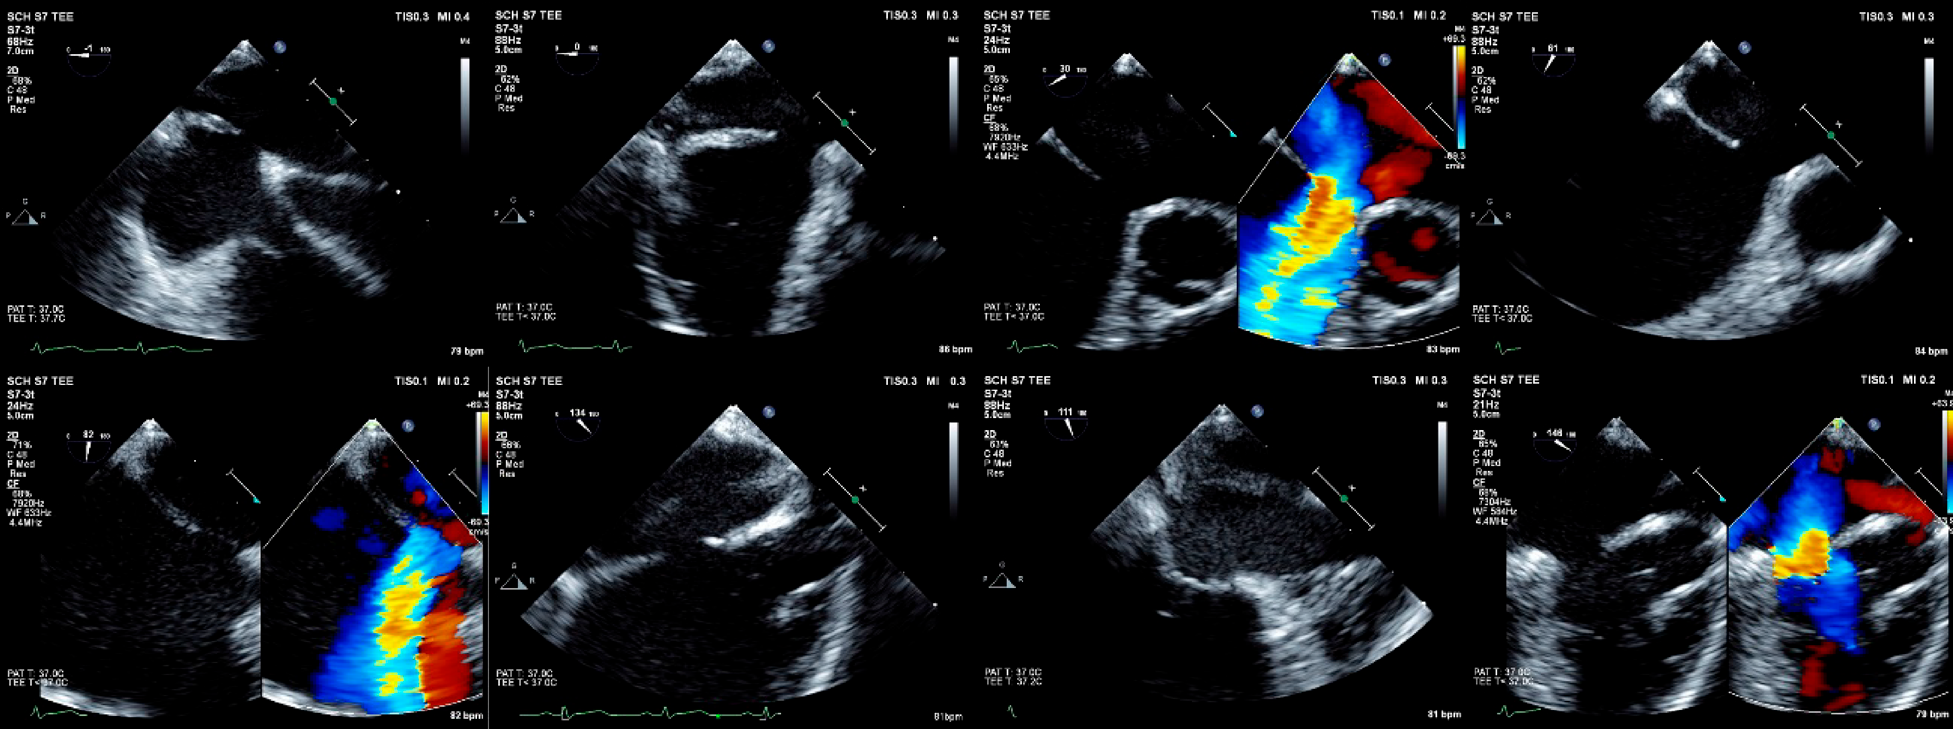

Fig. 2 経食道心エコーでの欠損孔の観察

6歳児例.心臓MRIで体肺血流比1.7.経食道心エコーでの各角度での欠損孔の周辺縁(rim)の観察.前上縁欠損で,大動脈周囲縁が少ないが,その他の周囲縁(房室弁縁,後縁,後下縁,左房天井,上下大静脈縁,冠静脈洞縁,房室弁縁,肺静脈縁)は5 mm以上であった.

ワイヤーメッシュ型デバイスは,通常,左房内で左房ディスクを展開し,中隔上までひきつけ,残るウエスト部,右房ディスクを展開し,中隔を挟み込むように留置する(Fig. 4-1, 2).ワイヤーフレーム型デバイスでは,左房内での前進に注意しながら左房ディスクを完全に展開すると漏斗形状となるため,この状態で中隔上までひきつけ,さらに右房ディスクを展開すると,両ディスクが平面上となり中隔を把持し留置される(Fig. 4-3).欠損孔が大きい場合,大動脈周囲縁が広く欠損する場合,左房が小さい場合などでは,通常の展開では閉鎖栓が右房側に脱落してしまうことがある.この場合には,肺静脈アプローチ(特に右上肺静脈)やバルーン,ワイヤーアシストなどの方法が用いられる.

Fig. 4 留置手技

1)7歳児例.MRIによる体肺血流比2.6, enface viewでの欠損孔は20.8 mmであった.経食道エコーでの欠損孔径は,18.0×16.0 mm.周辺縁は,大動脈縁は欠損していたが他の部位では5.0 mm以上であった.ストップフロー法によるバルーンサイジングにて欠損孔径は20.5 mm.Occlutech Figulla® FlexII Occluder21 mmを選択.上段は,左から展開された左房ディスク,展開中の右房ディスク,中隔を挟み込んでの留置.下段は左から右房側へ引き付けるwiggle, 左房側に押し込むwiggle, リリース後の閉鎖栓.2)7歳児例.Fick法による体肺血流比2.7.経食道エコーでの欠損孔径は,16.5×15.4 mm.周辺縁は,大動脈縁2.7 mm以外は5.0 mm以上であった.ストップフロー法によるバルーンサイジングにて欠損孔径は20.4 mm.Amplatzer™ Septal Occluder 20 mmを選択.上段は,左から右上肺静脈方向からのアプローチ,展開された左房ディスク,中隔への引き付け.下段は,左から展開中の右房ディスク,中隔を挟み込んでの留置,リリース後の閉鎖栓.3)11歳児例.Fick法による体肺血流比2.0.経食道エコーでの欠損孔径は,10.3×9.7 mm.周辺縁は,大動脈縁2.5 mm以外は5.0 mm以上であった.ストップフロー法によるバルーンサイジングにて欠損孔径は13.2 mm.GORE® CARDIOFORM ASD Occluder 32 mmを選択.上段は,a)左房内に到達したデリバリーカテーテル,b–d)左房ディスクの展開,e)中隔への引き付け.下段は,f–h)右房ディスクの展開,i)展開後のディスク形態.左右のディスクの直径が同程度で明確に分離され,ウェストがはっきり観察される,j)ロック後の閉鎖栓.矢印部にロックループが確認される.

留置後は,エコーで,周囲縁の把持状況,周辺組織との接触・圧迫様式,遺残短絡等を確認し,デバイスの脱落,エロージョンと呼ばれる心侵食,遺残短絡,上下大静脈や肺静脈,冠状静脈洞からの血流阻害を予防する.さらに,wiggleと呼ばれるケーブル,シースごとデバイスに押し引きを加える動作により,デバイスの脱落の有無を確認する.ワイヤーフレーム型デバイスでは,さらにロックと呼ばれる操作によって,デバイスへのデリバリーシステムによる張力を排除した状態でも評価を行う.問題がなければ,デバイスをリリースし手技は終了となる.